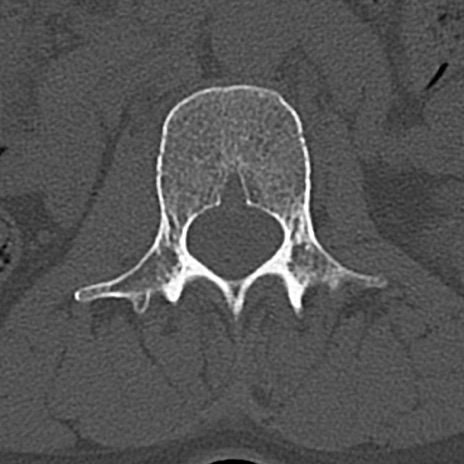

腰椎CT

横断像と矢状断像